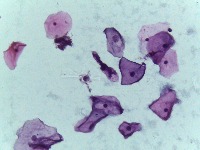

Medical Diagnostics: This model can be used in the healthcare industry to provide high-speed automated analysis of pathology slides, determining whether cells are normal or abnormal, and assisting in diagnosis of various diseases such as cancer.

Scientific Research: Researchers studying cell biology or genetics can use this AI model for their studies on cellular abnormalities and diseases. This can accelerate the onset of breakthroughs in medical science.

Pharmaceutical Applications: Pharmaceutical companies can use this model in drug discovery and development process. By identifying how different medications affect normal and abnormal cells, they can speed up and enhance their research.

Educational Tool: This AI model could serve as a rich educational tool in courses related to biology, medicine and health sciences, helping students to visualize and understand differences between normal and abnormal cells.

Personalized Medicine: This model can be used to analyze patients' cells to create personalized treatment plans. Understanding an individual's cellular structure could help healthcare professionals tailor treatments to the patient's specific needs.